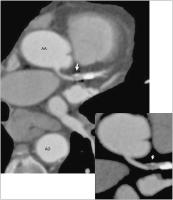

Abbildung 1: Koronare CTA. Darstellung der A. coronaria dextra (RCA) mit hochgradiger (> 90 %) Stenosierung – curved multiplanar reformation, MPR: proximal wenige cm nach Abgang aus der Aorta (Segment 1) demarkiert sich schwarz eine lipidhaltige Plaque (schwarzer Pfeil) mit deutlich niedrigeren CT-Dichtewerten (51 Hounsfield Units, HU) im Vergleich zum intraluminalen Kontrastmittel (288 HU). Im transversalen Schnitt durch die RCA (schwarzer Pfeil) erkennt man deutlich eine Dreischichtung: das mittlere Level (schwarz) entspricht dem lipidhaltigen Plaqueanteil, darüber (hell) das hochgradig (> 90 %) stenosierte Gefäßlumen und darunter der kalzifizierte Plaqueanteil (455 HU).

Abbildung 4b: Rezidivstenose bei Zustand nach Stentimplantation in der proximalen LAD: unmittelbar vor dem Stent zeigt sich eine lipidhaltige Plaque (weißer Pfeil). AA = Aorta ascendens; AD = Aorta descendens